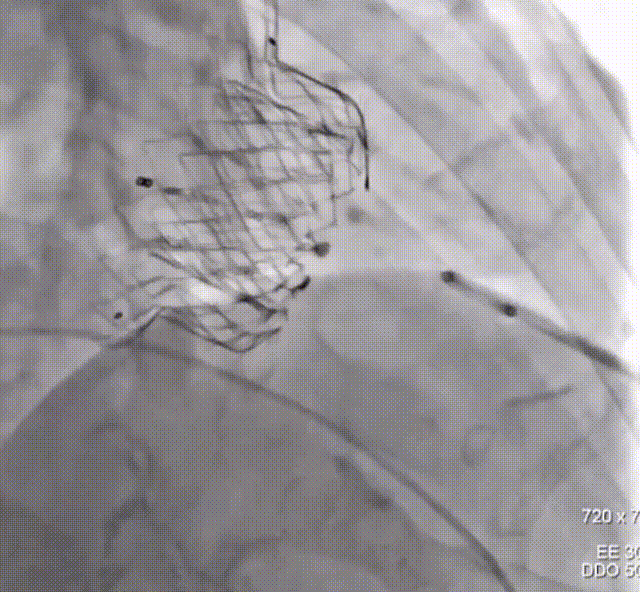

术中超声瓣膜释放

术中介入瓣膜顺利释放

术后介入二尖瓣瓣膜位置合适、瓣膜形态完整、有效瓣口面积3.7cm²,介入二尖瓣平均跨瓣压差3mmHg,无二尖瓣狭窄、无二尖瓣中心反流、无二尖瓣瓣周漏。手术顺利结束,患者术后24小时即离开监护室,回到普通病房。